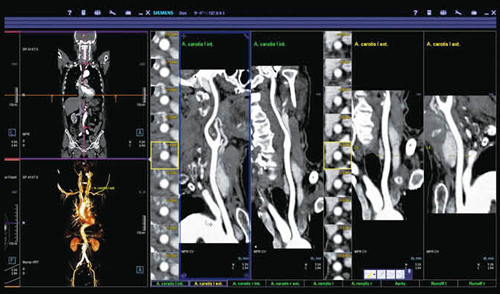

読影フローとしてまず,CT Vascular Analysisによって血管系の評価を行っているが,頸動脈,腎動脈,ステントなどの血管がすでに選択された状態で画面が立ち上がり,それぞれの血管の様子がスムーズに確認できる(図3)。この症例では,run-offやステントの状態も良好に描出されている。ただ,詳細に見ると下腸間膜動脈を介するtypeⅡのエンドリークが認められた(図4)。同時に,肺野の評価は,MM OncologyのCT Lung Careで行ったが,こちらも画面を起動すると,すでに肺野の結節が自動的に拾い上げられており,肺野の転移性病変についても,短時間で読影が行える(図5)。

図3 syngo CT Vascular Analysisによる血管解析とsyngo CT Lung CARE

主要血管の状態を直ちに確認することができる。